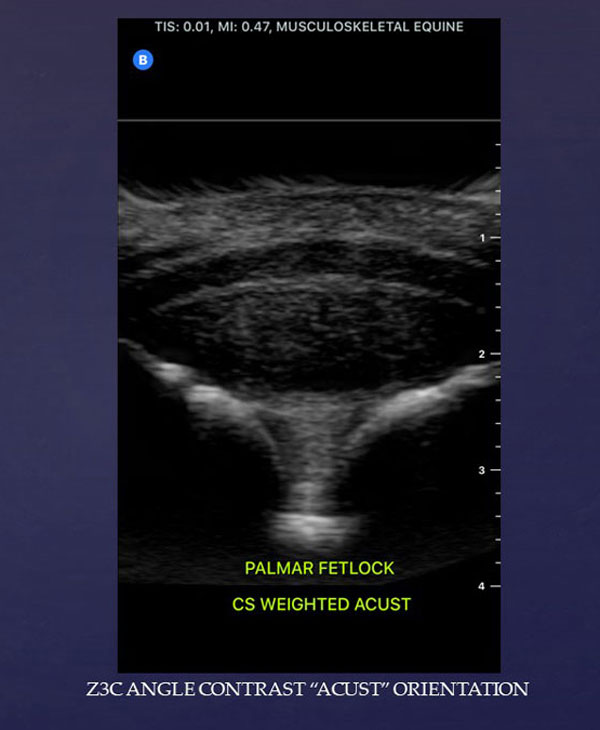

Palmar-fetlock-weighted-ACUST-Slide2-600V

Butterfly Equine Ultrasound Tips: Angle Contrast "ACUST" Imaging